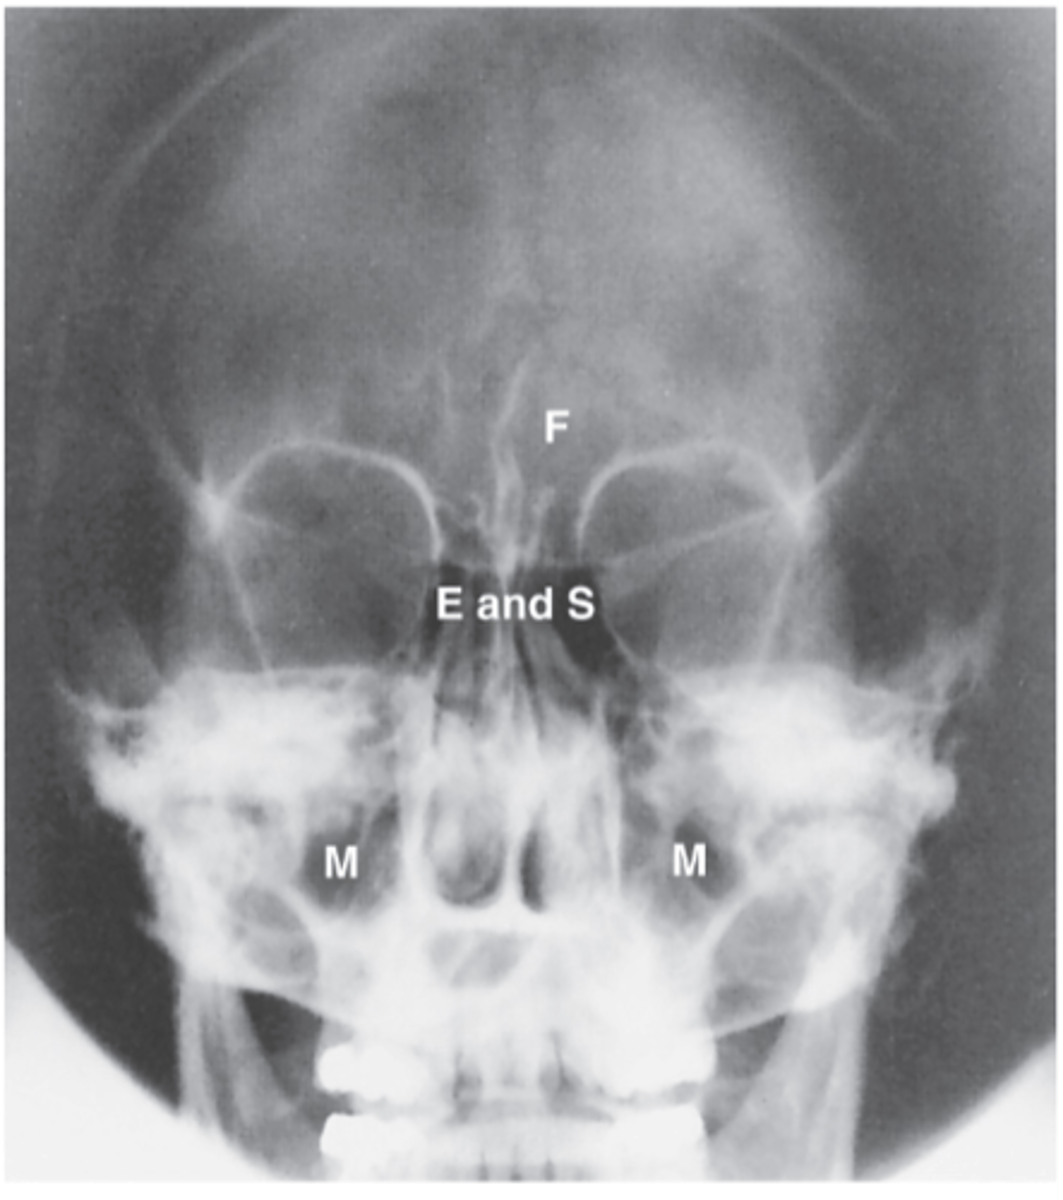

PA axial (Caldwell Method)

What projection is this?

CR exits the nasion & 15 degree caudal angle

What is the CR for PA axial (Caldwell Method)?

OML perpendicular to IR

What line should be perpendicular to the IR for a PA axial (Caldwell Method)?

Interpupillary line (IPL)

What line is parallel to the IR for a PA axial (Caldwell Method)?

Frontal and Ethmoid

What sinuses are clearly demonstrated on the PA axial (Caldwell Method)?

Lower 1/3 of orbits

Where are the petrous ridges located in a PA axial (Caldwell Method) radiograph?

Ethmoid Sinus

E

Sphenoid sinus

S

Maxillary sinus

M

Frontal sinus

F